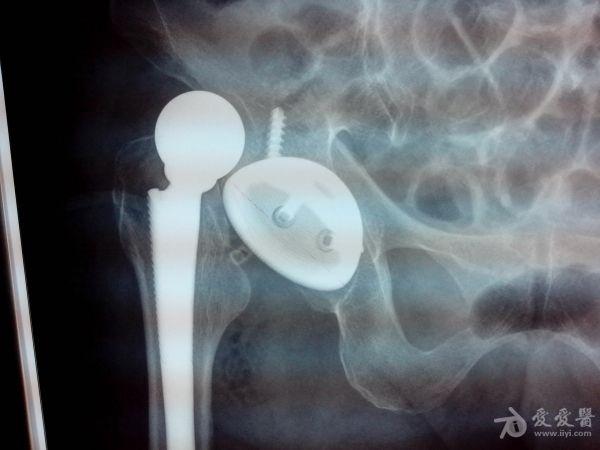

患者为75岁老年女性,因反复右髋部疼痛8+月,不能行走10+天入院。查体主要是右髋关节的压痛、叩痛,关节活动受限,右下肢无明显短缩。入院行X线片检查后发现右股骨颈陈旧性骨折(头下型)。追问病史发现患者在数年前曾有右髋部跌伤史,由于能忍痛行走,所以没有就诊。经科室讨论诊断为“右股骨颈头下型骨折(陈旧性),右股骨头缺血性坏死”。在完善术前检查后予在全麻下行“右人工全髋关节置换术”。术中顺利,时候予头孢呋辛、克林霉素抗感染治疗,低分子肝素钠抗凝治疗,以及对症支持治疗。让人最担心的事情出现了,术后不到24小时,患者右髋关节脱位了,并且出现的是前脱位,遂即在全麻下行手法复位,复位后外展、外旋、屈曲髋关节均无脱位发生,甚至轻度内收内旋都不脱位。以为是患者体味的问题。随之出现的是之后的10天左右时间里,患者右髋关节反复脱位,均是前脱位,并且发现在右下肢位于外展位时发生脱位,稍微牵引右下肢并内收既能复位。患者于今日上午再次发生脱位,脱位发生在右下肢伸直、外旋约5°,在牵引并内旋后可以轻松脱位,再伸直并轻微外旋又能轻松脱位。反复观看患者的X线片,考虑原因1、髋臼杯前倾角过大(粗略测了下大概有24°多);2、股骨柄过短所致。本打算做翻修,但向上级医院的教授请教后(教授并未直接看到患者),建议予髋人字石膏外固定3个月,于是在下午做了石膏固定。目前的问题是:1、石膏外固定三个月有效果吗?2、三个月去除石膏后在发生脱位怎么办?3、**已经不可避免,请各位老师看看我们主要的问题在哪里?是不是我们所考虑的前倾角和股骨柄的问题?4、手术指征是否存在问题?手术是我们一位德高望重的老师做的,大家都觉得很遗憾,最近我们科所有的医生都被这个事情给弄得郁闷了,气氛好压抑。

1、手术前的片子。

2、术后第一次脱位的片子。

3、复位后复查的片子,这个也是唯一一张关节在位时拍的片子,之后患者就出现反复脱位。

4、最后一次脱位的片子。

髋臼臼杯前倾外展没问题。问题可能在于:1、股骨柄前倾角过大。2、股骨头短(以至于轻度牵引外旋就脱位,本里可能性很大,因为是前脱位)。

1.髋臼外展角过大,目测超过60度以上,前倾角目测也过大2.假体柄与小转子夹角过大3.股骨距过短个人经验:闭合伤口前应常规行髋关节过伸过屈试验,牵拉髋关节感觉下头臼距离,分层严密缝合创面